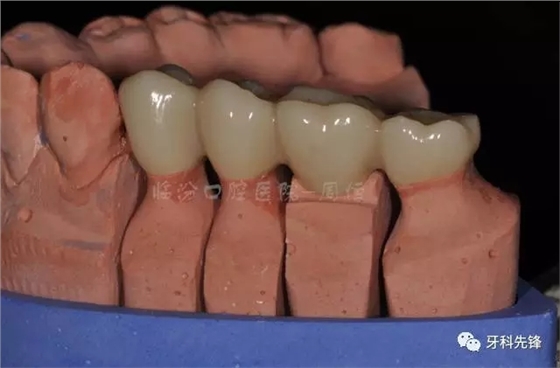

圖13牙體預(yù)備模型照

640.webp (17).jpg